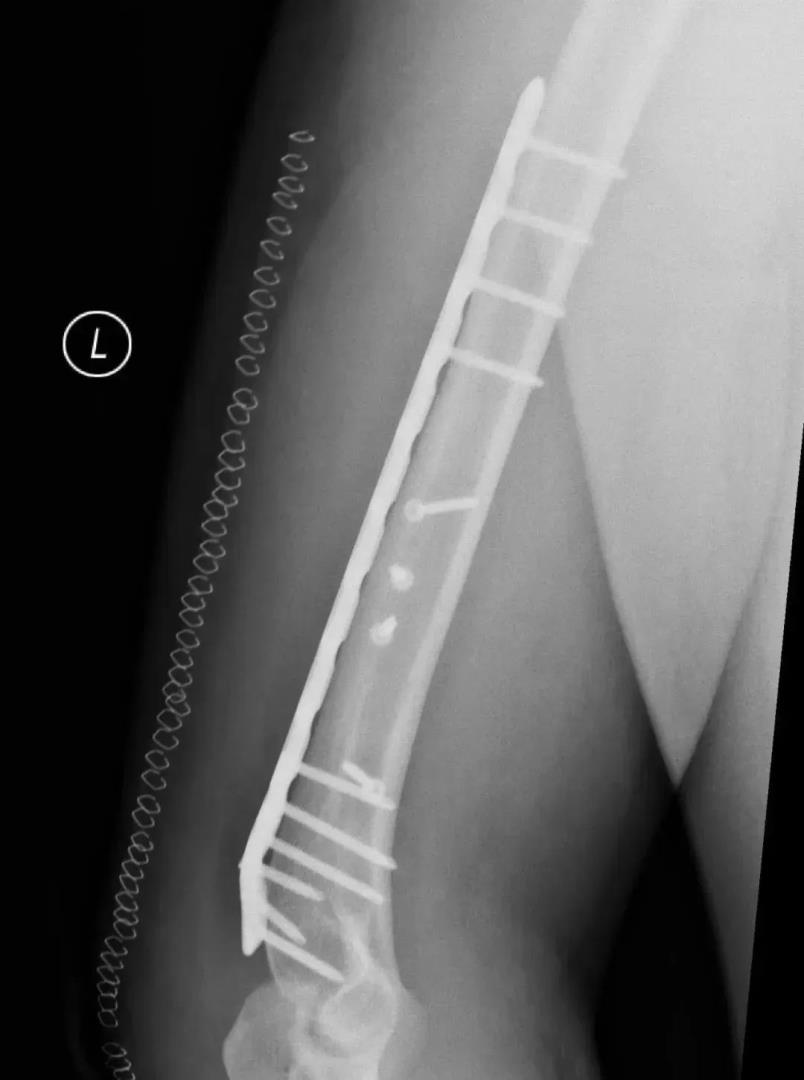

经过影像检查,小潘是左侧肱骨干骨折,主管医生说先左上臂夹板固定后再行手术。在完善术前检查后,小潘如期进行左肱骨骨折切开复位钢板螺钉内固定术,住院期间给予对症治疗后,现手术创口愈合良好,拆线后出院了。出院那天小潘说:“掰手腕这个事情,以后不约!”

肱骨干骨折的治疗方法包括保守治疗、闭合复位髓内钉内固定术和切开复位钢板螺钉内固定术等多种方式。采用非手术治疗时,可对患肢进行悬垂石膏固定或行闭合复位后使用上臂U型石膏固定,2-3周后解放肘关节,使用功能支具固定10-12周。由于扳手腕导致的肱骨干骨折几乎均为肱骨远端三分之一螺旋形骨折,闭合复位髓内钉内固定术不适合这类骨折,切开复位钢板螺钉内固定术是这类骨折的最佳的手术治疗方式。肱骨干骨折的治疗方式需要考虑患者的骨折类型、损伤程度、功能需求等多种因素,因此,患者应咨询专业骨科医生后决定具体治疗方式。